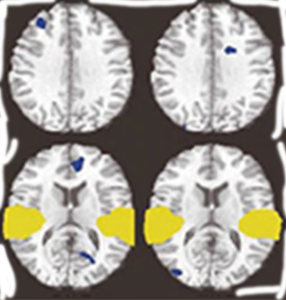

마음챙김 수행자

휴식중

마음챙김중

1968년, 마음챙김의 효과를 과학적으로 검증하기 위한 연구가 8주간의 수련을 통해 진행되었으며, 그 결과 대뇌피질 좌측 전두엽의 활성 증가가 확인되었습니다. 연구에서는 스트레스로 인한 교감신경계의 과잉 활성은 완화되고, 안정 상태를 조절하는 부교감신경계의 기능이 상대적으로 우세해지는 변화가 관찰되었습니다. 특히, 마음챙김 수행자의 전두엽 활성 수준은 일반인보다 높게 나타났습니다. 이러한 연구 결과를 바탕으로, 1975년 하버드 의과대학에서는 일반인을 대상으로 한 마음챙김 치료법 「이완반응」을 도입하였습니다.